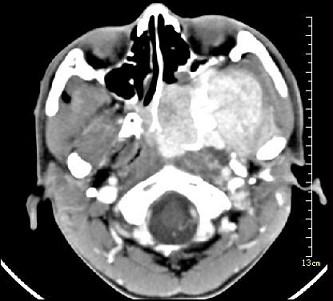

问题 男性,19岁,左侧鼻腔反复出血1年余,CT、MRI扫描如图所示,请选择最可能诊断()

选项 A.鼻息肉 B.鼻咽腔脓肿 C.鼻咽部青年纤维血管瘤 D.鼻咽癌 E.鼻咽部淋巴瘤

答案 C